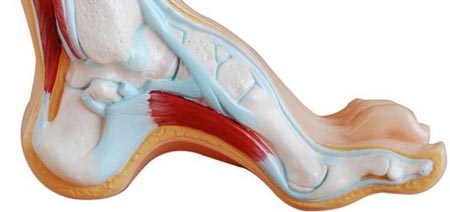

درد کف پا اصطلاح مورد استفاده برای توصیف علائمی است که در زیر قوس پا رخ میدهد. درد کف پا معمولاً به دلیل التهاب بافت نرم در وسط پا است. کف پا از باند بافت فشردهای ایجاد شده است که استخوان پاشنه را به انگشتان پا متصل میکند. این بافت فاشیای کف پا نامیده میشود و در حرکت مناسب پا و انتقال وزن از پاشنه تا انگشتان پا نقشی مهم دارد. زمانی که بافت کف پا ملتهب و تحریک میشود، حتی حرکات ساده ممکن است بسیار دردناک باشد.

شایعترین علت درد کف پا التهاب فاشیای کف پا است. التهاب فاشیای کف پا نامی است که التهاب باند فیبری بافت را توصیف میکند و باعث اتصال پاشنه به انگشتان پا است. علائم التهاب فاشیای کف پا شامل درد در اوایل صبح و درد هنگام پیادهرویهای طولانی و یا ایستادن طولانیمدت است. درد کف پا در صبح زود به این دلیل است که فاشیای کف پا در طول شب منقبض و تنگ میشود.